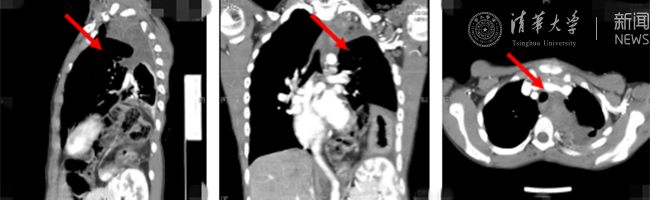

星空online(中国)网8月30日电(通讯员 杨峰)如图中所示,本是正常人心脏、左肺的位置,被发于神经鞘的巨大肿瘤占据,导致一位刚满12岁的男孩胸痛、咳嗽、呼吸困难。近日,北京清华长庚医院神经外科与胸外科联手,由神经外科王贵怀主任主刀,成功为男孩切除胸腔巨大神经鞘肿瘤。

患者胸腔内巨大的肿瘤。

半年前,患者经常会出现胸痛、咳嗽和呼吸困难,在当地医院检查发现左侧胸腔巨大占位,左肺及心脏明显受压。王贵怀大夫接诊,仔细查体了解病情,并反复认真阅片后,认为左侧胸腔巨大肿瘤来自于胸椎椎管内,神经鞘瘤可能性大。该肿瘤体积巨大,占据绝大部分胸腔空间,压迫左肺、纵隔大血管及膈肌。